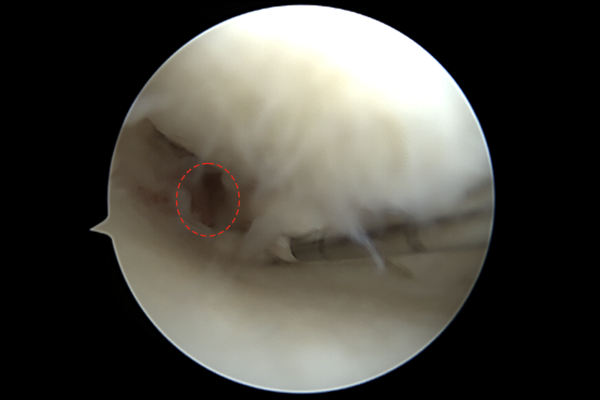

무릎 내시경(관절내시경) 사진에서 수술도구로 들췄을 때 빈 공간이 있는 것이 확인됩니다.